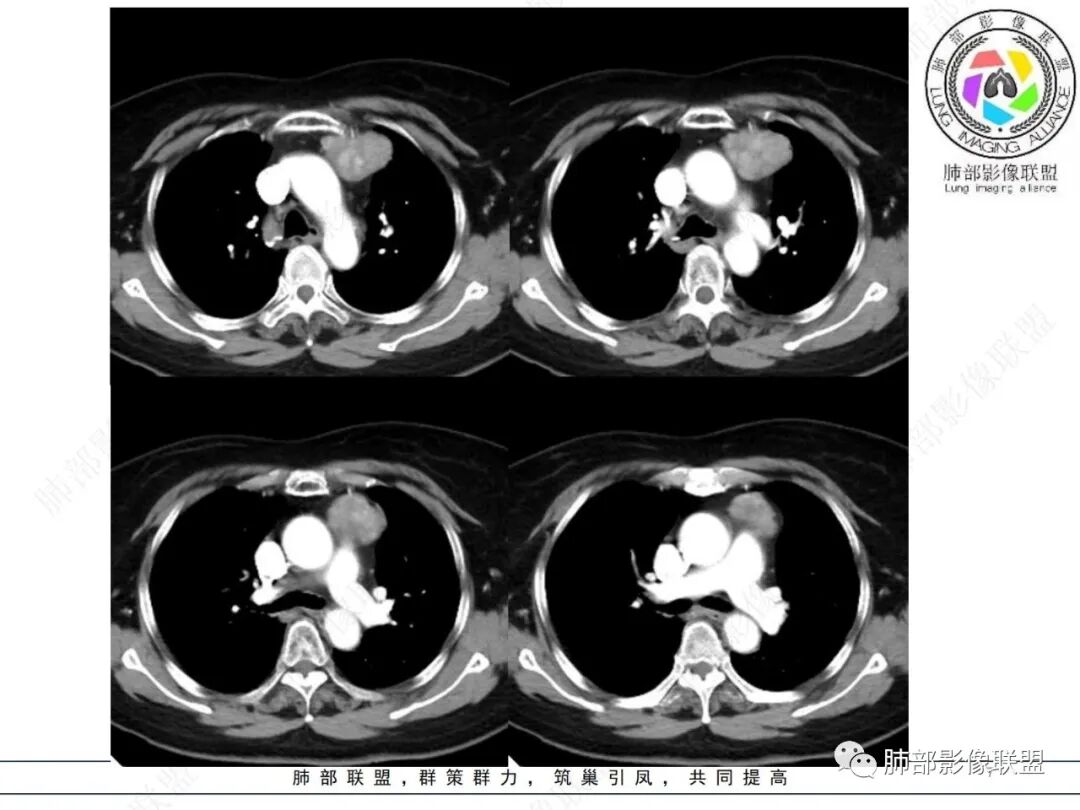

前上纵隔偏左侧实性病灶,边界清楚,边缘彭隆,浅分叶,内部密度均匀,未见钙化、脂肪密度,周围脂肪间隙清晰。

包膜完整,纤维分隔,结节感明显

平扫密度较均匀,增强渐进性不均匀强化,内见低密度纤维分隔。未见肿大淋巴结。未见胸腔积液。